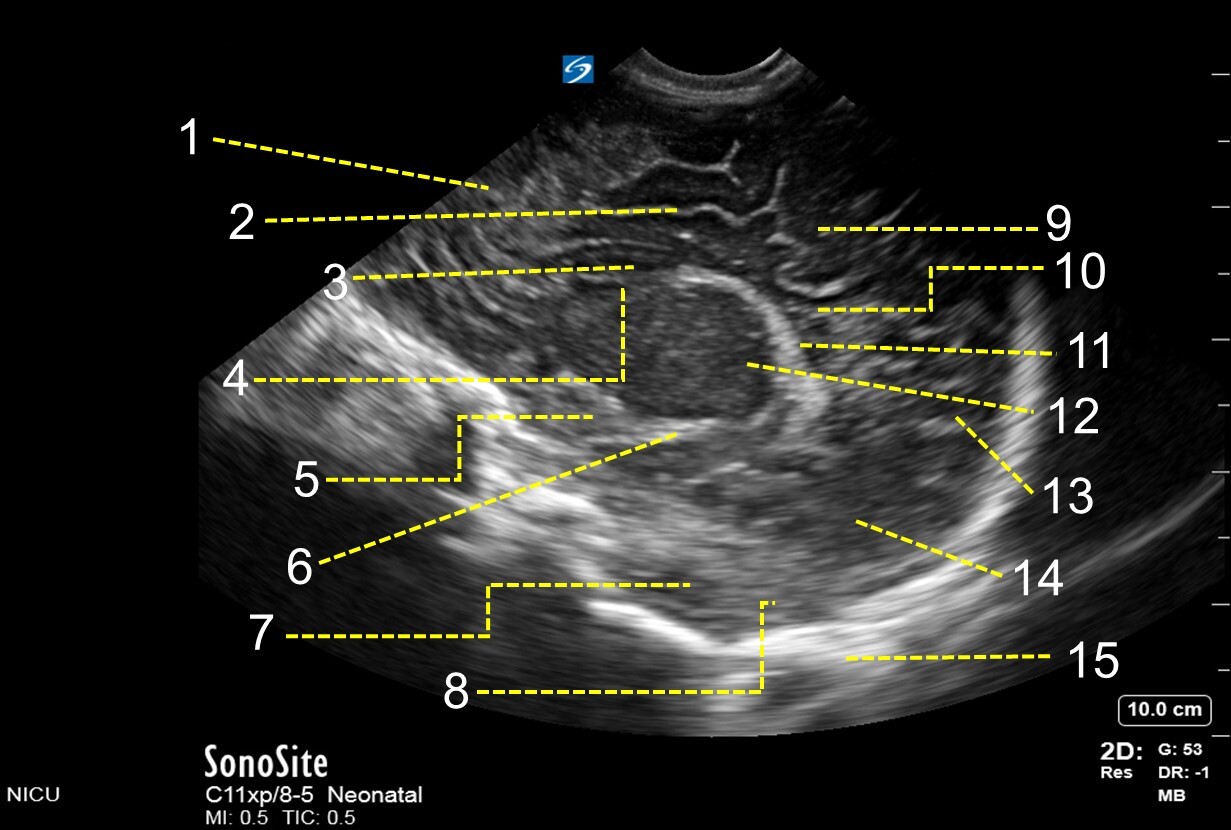

1. Frontal Lobe

2. Cingulate Sulcus

3. Frontal Horn of Lateral Ventricle

4. Caudate Nucleus

5. Para Hippocampal Gyrus

6. Temporal Horn of Lateral Ventricle

7. Temporal Lobe

8. Cerebellar Hemisphere

9. Parietal Lobe

10. Body of Lateral Ventricle

11. Choroid Plexus

12. Thalamus

13. Parieto-occipital Fissure

14. Occipital Lobe

15. Skull